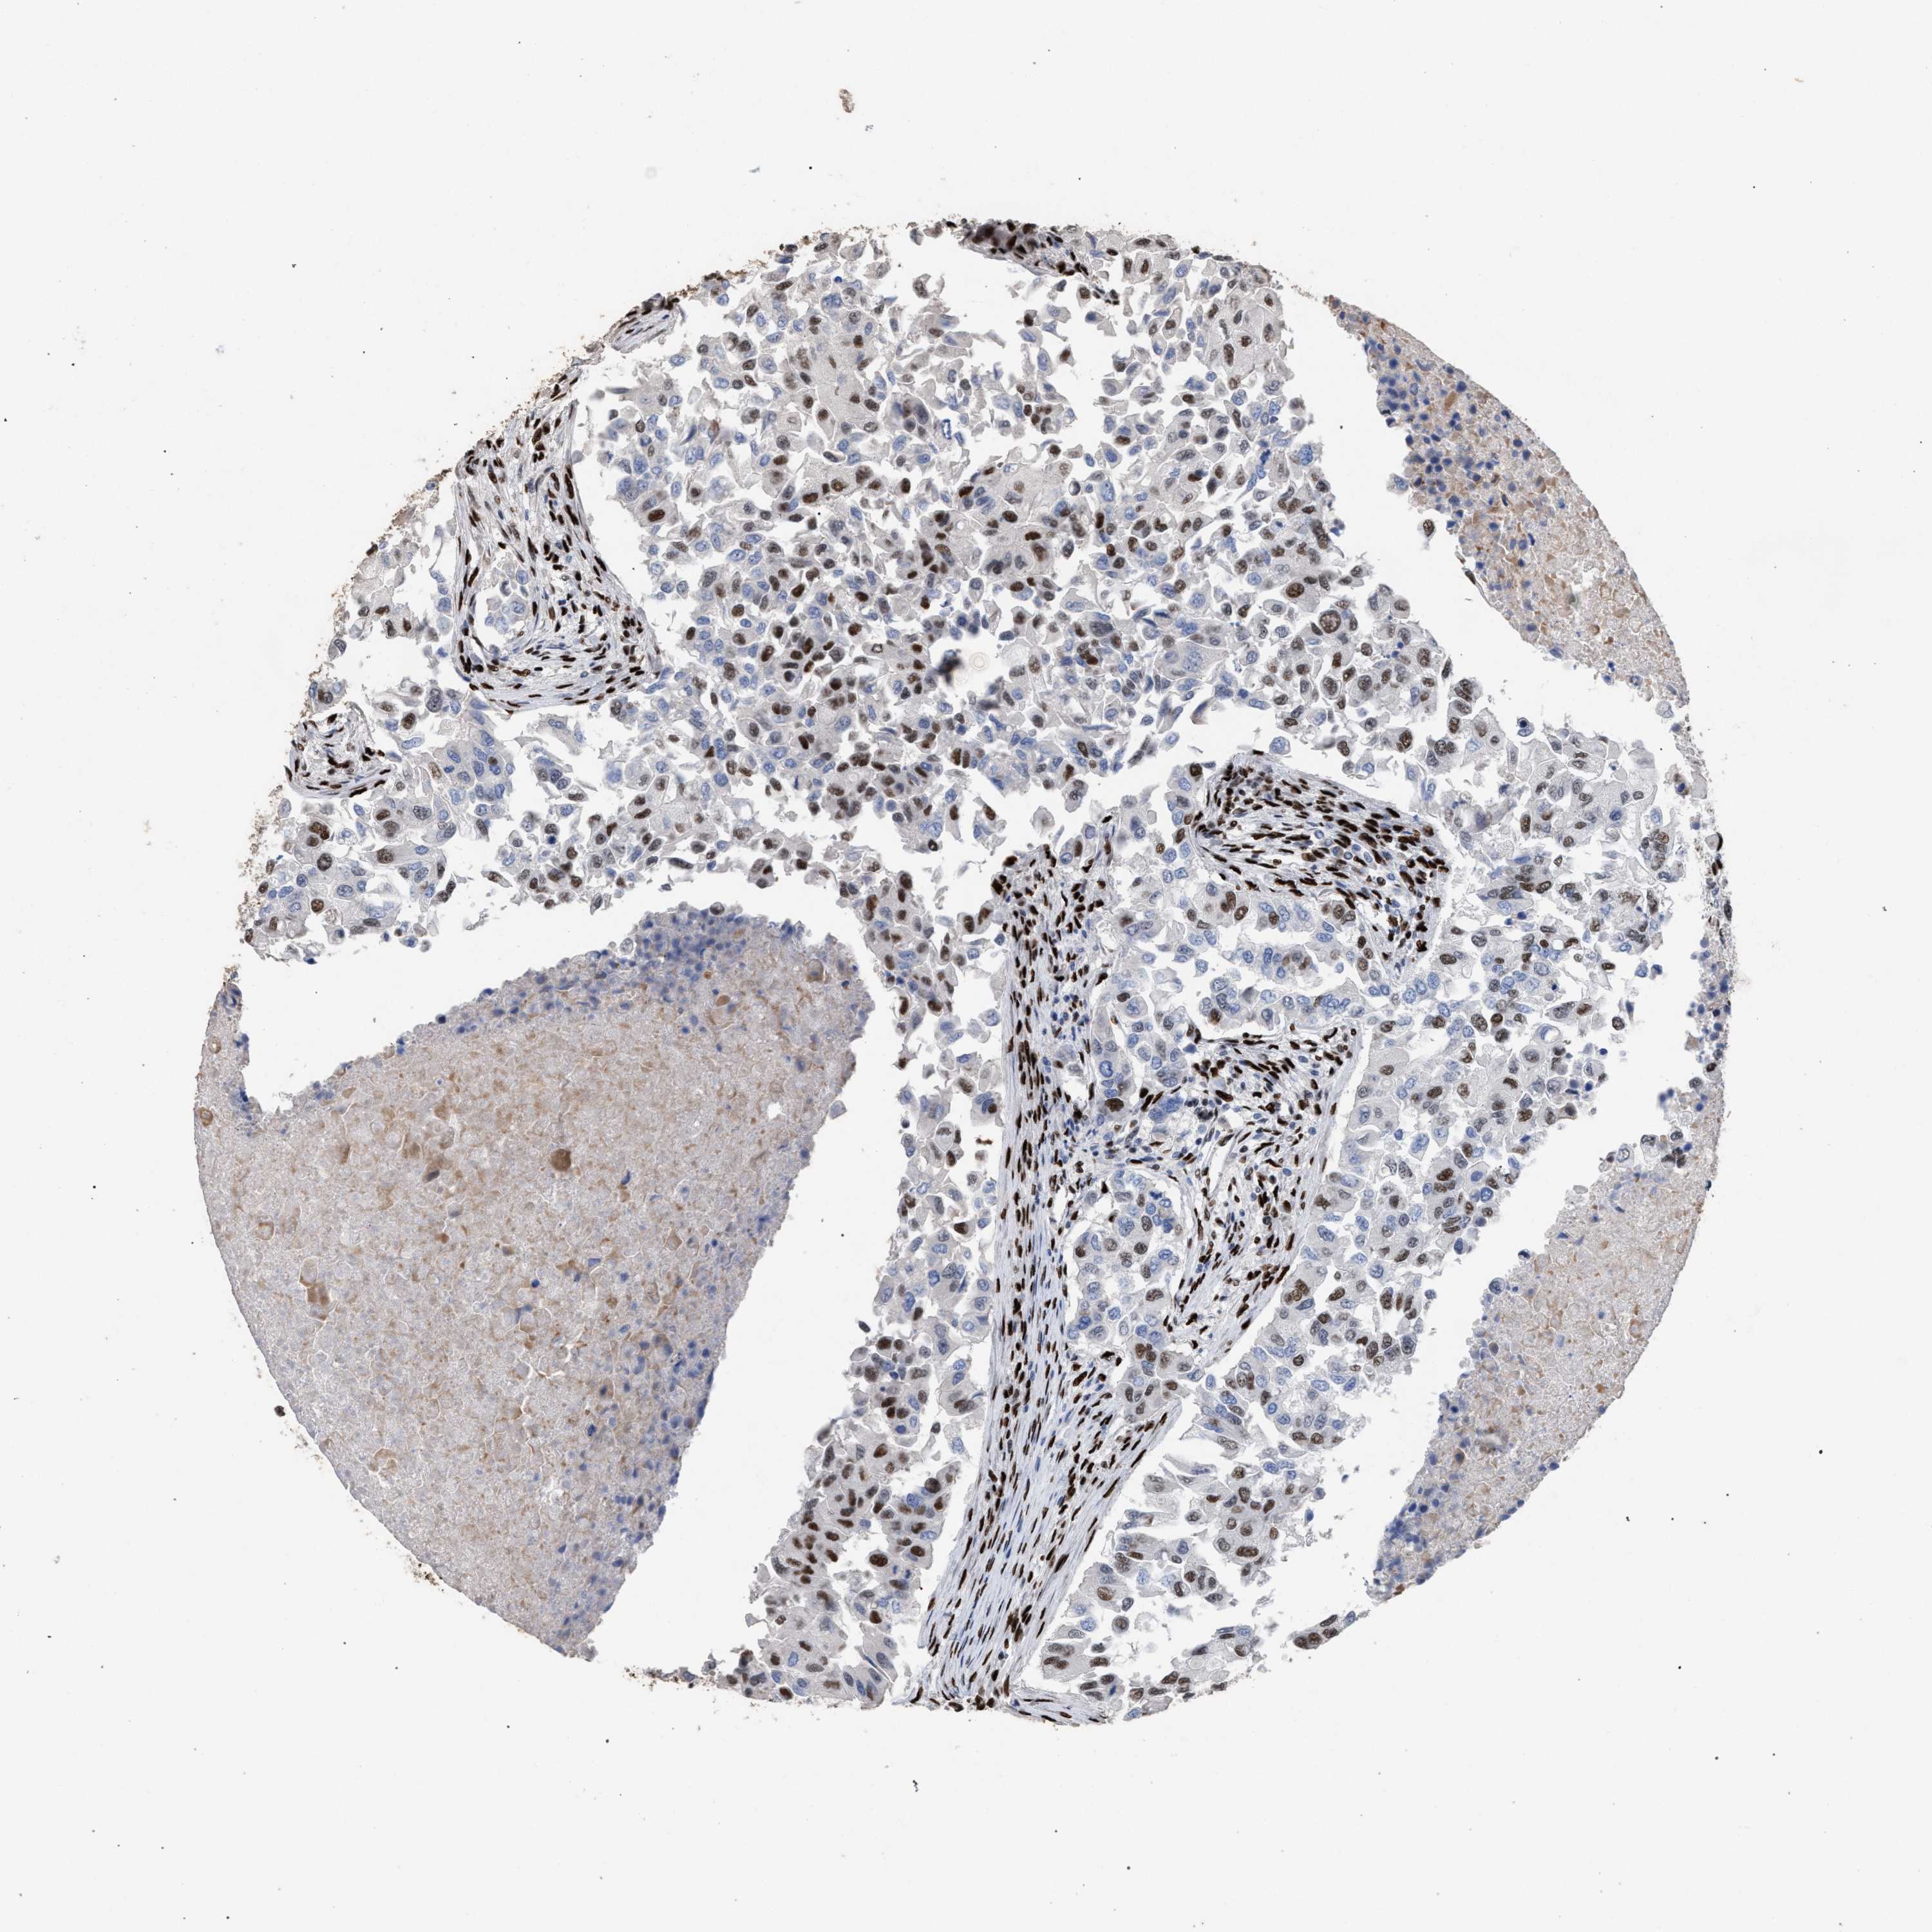

BRCA TCGA BRCA VALIDATION PROTEIN EXPRESSION